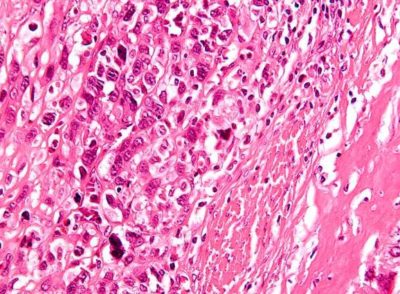

Al analizar los resultados de una biopsia, para certificar que una mujer padece una patología mamaria, existen dos alternativas, que efectivamente se trate de un cáncer invasivo (la evidencia suele ser muy evidente y aquí no hay posibilidad de mal interpretar el resultado), o que, por el contrario, el tejido está absolutamente sano y no existe el cáncer (los resultados aquí tampoco se prestan a interpretaciones erróneas). Sin embargo, entre un diagnóstico y otro, media una “zona gris”, en la cual los resultados de las biopsias no resultan del todo claros y surgen las dudas, porque no siempre estos estudios coinciden en el diagnóstico.

La investigación, que llevó siete años de estudio y análisis, constó de dos pasos. Primero, tres patólogos expertos examinaron las muestras de tejido de 240 mujeres y coincidieron con el diagnóstico. Luego, esas muestras fueron enviadas a otros 115 patólogos, menos experimentados, para corroborar si viendo la misma biopsia, coincidían en los diagnósticos. Y descubrieron que al tratarse de un cáncer invasivo, los patólogos menos experimentados, coincidieron con los de mayor experiencia, en el 96 % de los casos; es decir, aquí no hubo posibilidades de diagnosticar erróneamente. En cambio, en el extremo opuesto, cuando se trataba de patologías benignas, unos y otros patólogos concordaron en un 87 % de los casos. El inconveniente, surgió en la denominada “zona gris”. Cuando se presentaba un cáncer no invasor, hubo disidencias en 1 de cada 5 diagnósticos. Y cuando se trataba de diagnosticar atipia, un resultado que indica que las células son anormales, pero no cancerosas, solo hubo acuerdo en la mitad de los casos.

Para realizar el estudio (biopsia), se aplica anestesia local y se efectúa sobre el pecho una punción con una aguja especial. Luego, esa aguja es guiada con la ayuda de un ecógrafo. Se extrae la muestra de parte del tejido sospechoso y se la envía al laboratorio. Allí se analizará el material recogido y se notificará el diagnóstico.